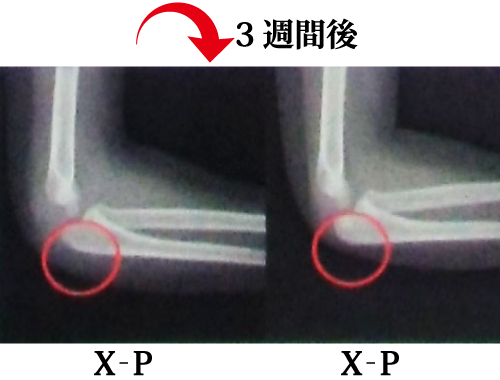

@レントゲン撮影による経過観察

・肘頭骨折